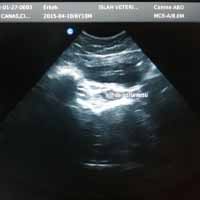

Bodrum Yalıkavak'taki veteriner kliniğimizde uygulanan iç hastalıkları cerrahi prosedürleri:

Bu cerrahi disiplin de yumuşak doku cerrahisi basit görünen fakat oldukça komplike operasyonları içinde barındıran bir cerrahi disiplindir. Hepinizin bildiği Kısırlaştırma operasyonu aslında bir iç hastalıkları cerrahisidir. Daha da detaylandıracak olursak; Yüksekten düştüğü için diyaframı yırtılan (Hernia Diaphragmatica) bir kedinin diyaframının tekrardan dikilmesi ve fonksiyonunun tekrardan kazandırılmasını da iç hastalıkları cerrahisi olarak tanımlıyoruz.